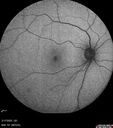

BRAO - plaques in vessels - GIF video of FA3 views78 year old female with vision loss for 1 week and old macular scar. Images show BRAO with plaques and FA shows occlusion.Oct 13, 2025

BRAO - plaques in vessels - GIF video of FA2 views78 year old female with vision loss for 1 week and old macular scar. Images show BRAO with plaques and FA shows occlusion.Oct 13, 2025